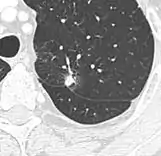

Thin slice and maximal intensity projection of a lung nodule, the latter better visualizing vascular convergence.[9]

• Vascular convergence is where vessels converge to a nodule without adjoining or contacting the edge of the nodule, and is mainly seen in peripheral subsolid lung cancers.[9] It reflects angiogenesis.[9]